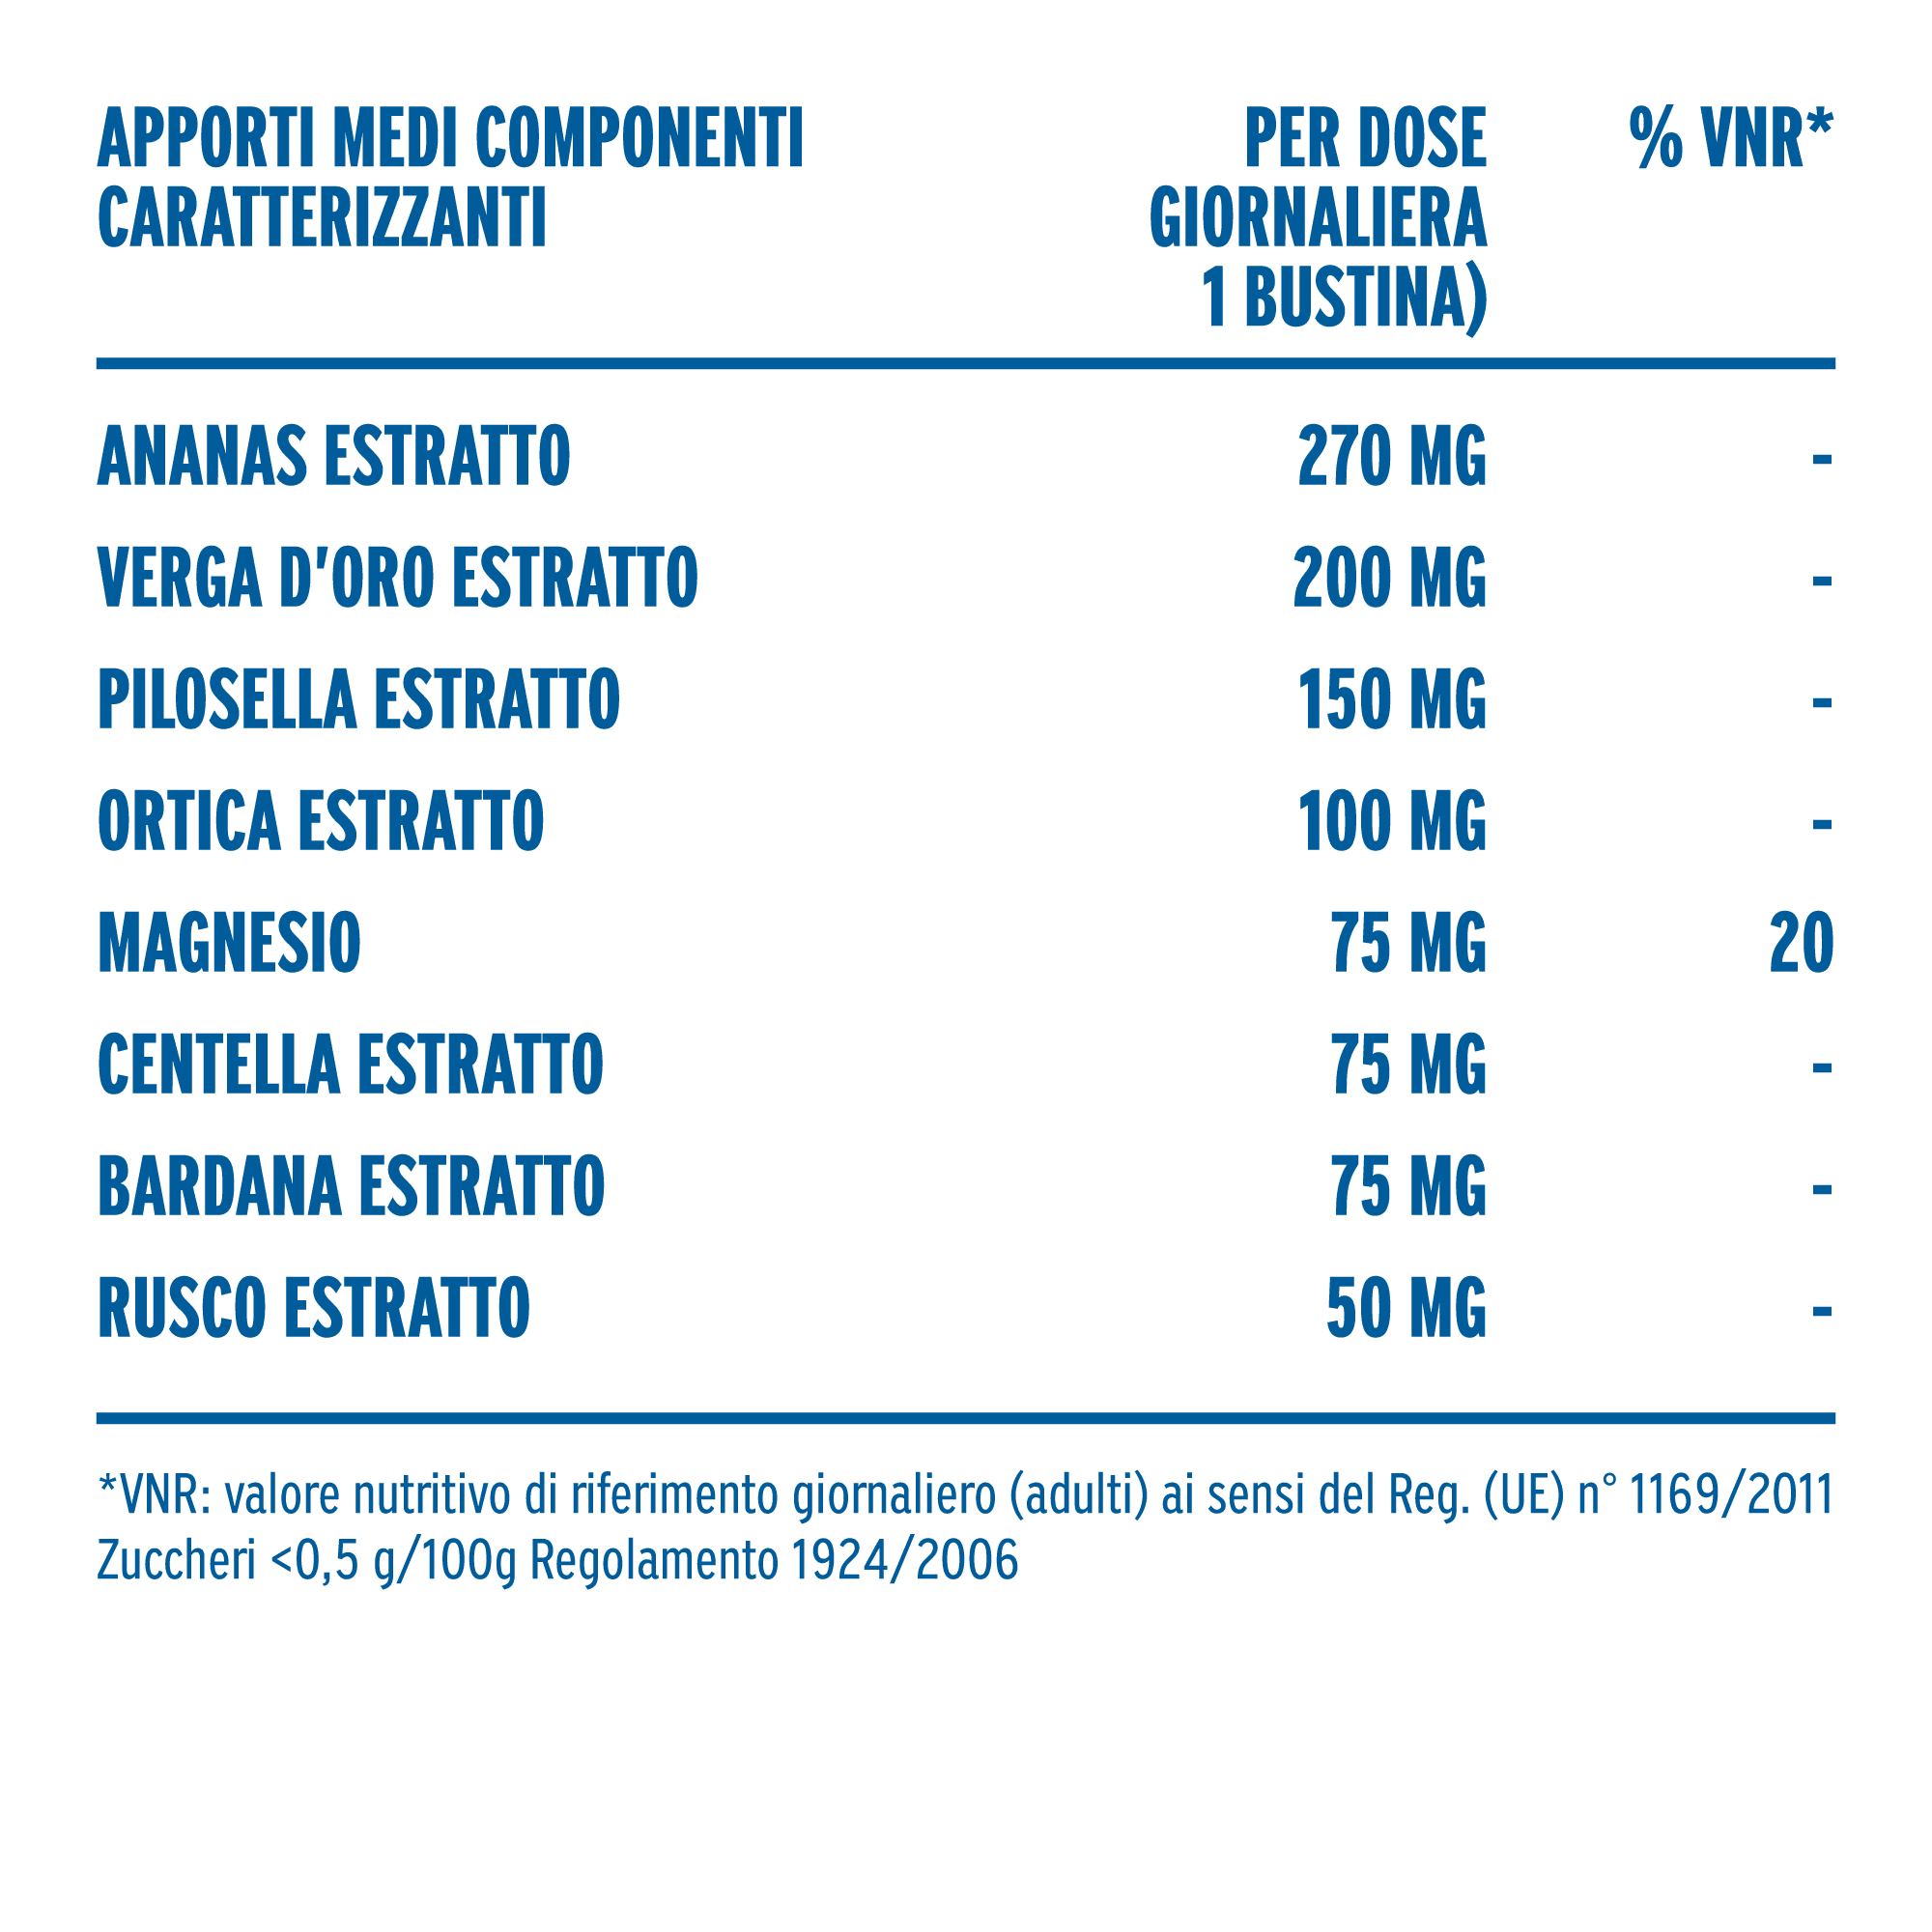

Zymerex Gonfiore Fluid è un integratore liquido in bustine, in formula concentrata con Drenolinph, un pool di 7 estratti naturali che stimolano l’azione drenante e detossinante dell’organismo, favoriscono la riduzione della sensazione di gonfiore e gambe pesanti, stimolano il drenaggio dei liquidi corporei e contribuiscono a una sensazione di leggerezza e benessere generale. Contiene inoltre Magnesio, per favorire l’equilibrio elettrolitico. Zymerex Gonfiore Fluid aiuta a bere più acqua. I glicosidi dello steviolo dolcificano naturalmente il prodotto senza incidere sui livelli glicemici.

Complesso erboristico concentrato e sinergico di 7 Fitoestratti (ananas, bardana, centella, ortica, pilosella, rusco, verga d’oro) in rapporto tra loro, ottenuti con metodi naturali, dalle particolari caratteristiche di funzionalità, con proprietà drenanti e depurative per l’organismo e che favorisce la riduzione della sensazione di gonfiore e gambe pesanti.

Acqua depurata; Magnesio citrato; cloruro di potassio; Ananas (Ananas Comosus (L.) Merr., maltodestrina) stipite estratto secco; acidificante: acido citrico; Verga d’oro (Solidago virgaurea L., maltodestrina) erba con fiori estratto secco; aroma; Pilosella (Pilosella officinarum Vaill., maltodestrina) erba estratto secco; Ortica (Urtica dioica L., maltodestrina) foglie estratto secco; Bardana (Arctium Lappa L., maltodestrina) radice estratto secco; Centella (Centella asiatica (L.) Urb., maltodestrina) foglie estratto secco; Rusco (Ruscus aculeatus L., maltodestrina) radice estratto secco; addensante: gomma di xantano; edulcorante: glicosidi steviolici da stevia; conservanti: sorbato di potassio e benzoato di sodio.